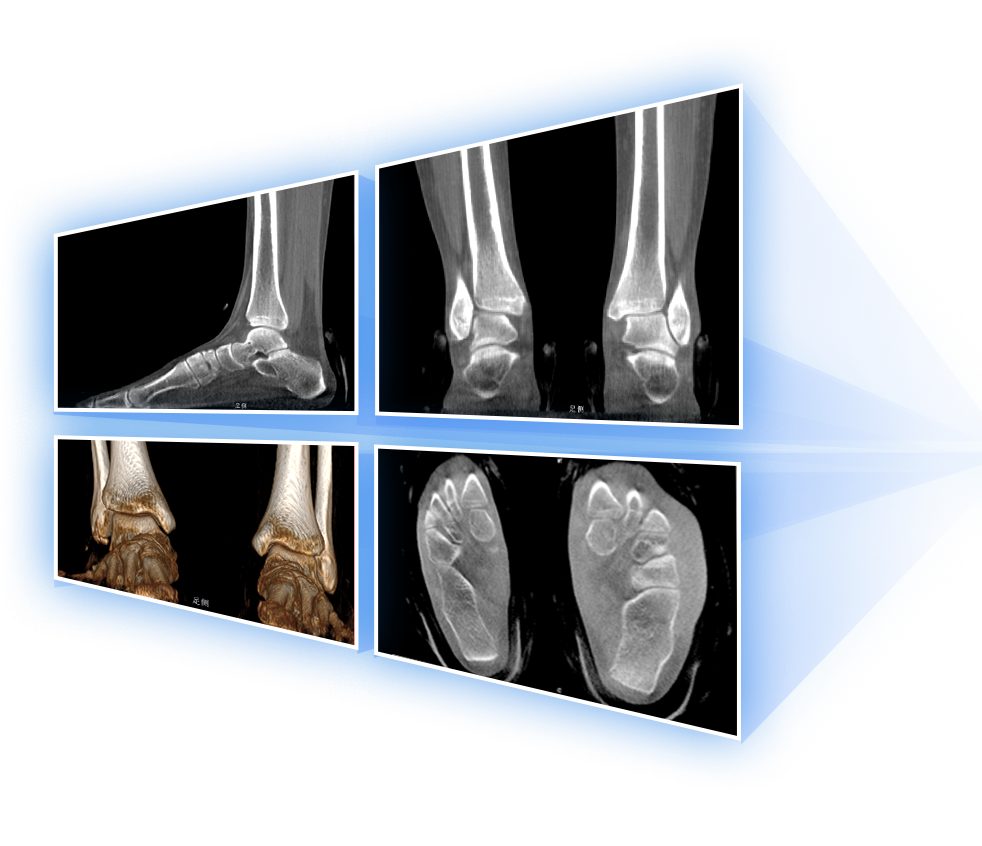

足踝

VR体绘制重建

FOV 250mm

FOV 350mm

关闭金属伪影校正

开启金属伪影校正